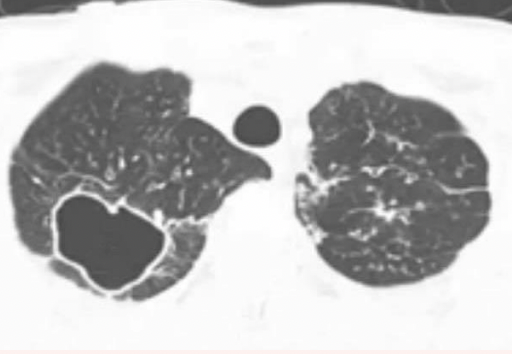

Q

qué se observa en una TAC con Tb?

A